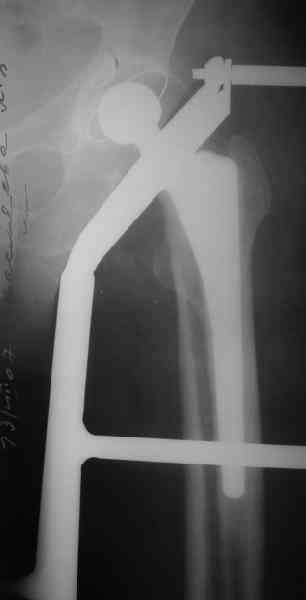

Представленные снимки неудачны ни по качеству, ни по обзорности. Классификационно предположительно Ванкувер В2. Накостный остеосинтез LCP с использованием монокортикальной фиксации в проксимальном отделе.

1. Представляющей наибольшую ценность из представленной информации следует считать фасные снимки №3и №4 (если считать по порядку). На снимке №3 не видны ни проксимальный отдел бедра с зоной (линией) перелома - наложение тени, ни дистальная зона (линия) перелома - область не захвачена. Снимок №4 демонстрирует дистальную линию перелома, но не показывает уровень конца ножки эндопротеза. В таких сучаях как способ можно выполнять снимок "с метками" - чтобы при при наложении снимков на негатоскопе иметь целостностное представление о всём сегменте от тазобедренного до коленного суставов.

2. Не совсем так. Перелом В2 (по C. Duncan и B.A.Masri, 1995) - перелом на уровне ножки эндопротеза или непосредственно дистальнее её конца с нестабильностью ножки, но хорошим качеством кости проксимального отдела бедра. Как известно, по статистике - наиболее часто встречающийся тип перипротезного перелома при первичном эндопротезировании. Очевидно - продольное раскалывание проксимального фрагмента в данном случае вызовёт нестабильность ножки.

3. Вопрос про достаточность сложный. Не исключён вариант применения серкляжных конструкций на проксимальном фрагменте, что, конечно, негативно отразится на отдалённых результатах. Пластина - бедренная прямая широкая, с подбором по длине. Доступ - латеральный, через fascia lata. Мы при эндопротезировании применяем доступ Хардинга - поэтому в подобном случае расширяли бы первоначальный доступ в дистальном направлении. Способ репозиции, имхо, по ситуации.